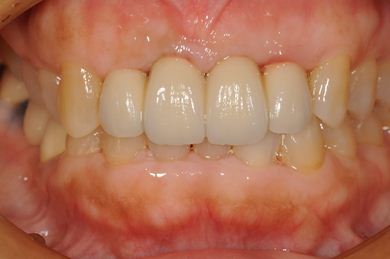

抜歯即日スピードインプラント治療

| 性別/年齢 | 女性 / 52歳 | ||||||||||||||||||||||||||||||||

| 主訴 | 歯周病で歯の位置がずれてしまった。 | ||||||||||||||||||||||||||||||||

| 治療内容 | インプラント2本(抜歯即日スピードインプラント)、メタルボンドセラミッククラウン4本 | ||||||||||||||||||||||||||||||||

| 総治療費 | 1,269,450円 | ||||||||||||||||||||||||||||||||

| 治療期間 | 10ヶ月 |